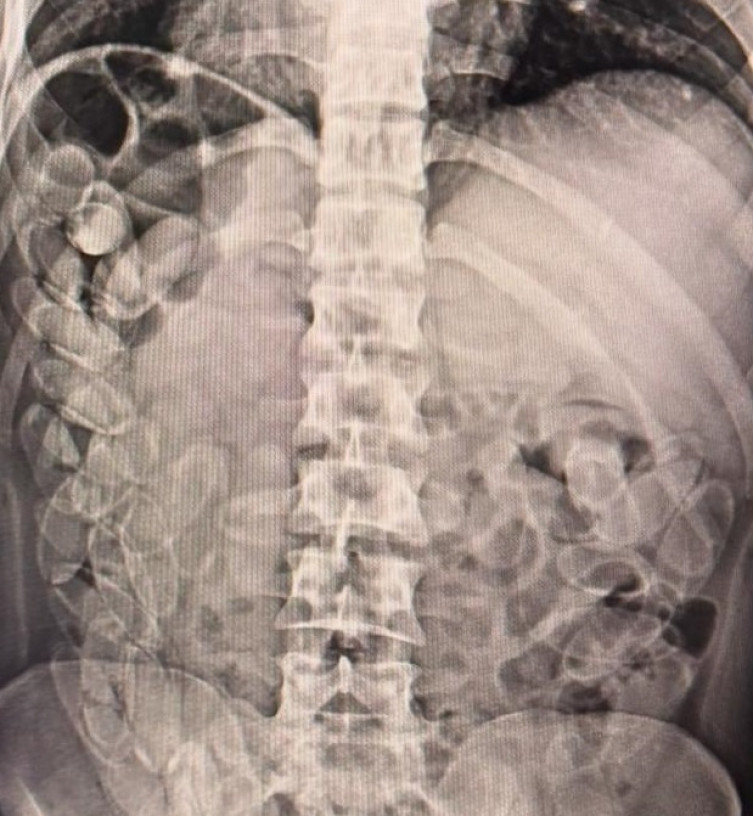

O restante havia sido ingerido pelos três homens, que, segundo imagens de raio-x, haviam engolido cerca de 100 cápsulas de droga cada um.

Os estrangeiros confessaram que levariam a droga até São Paulo e receberiam R$ 2.500,00 cada um pelo transporte. Eles foram encaminhados à Santa Casa de Corumbá para acompanhamento médico e, após expelir as cápsulas, seriam levados à Delegacia da Polícia Federal.